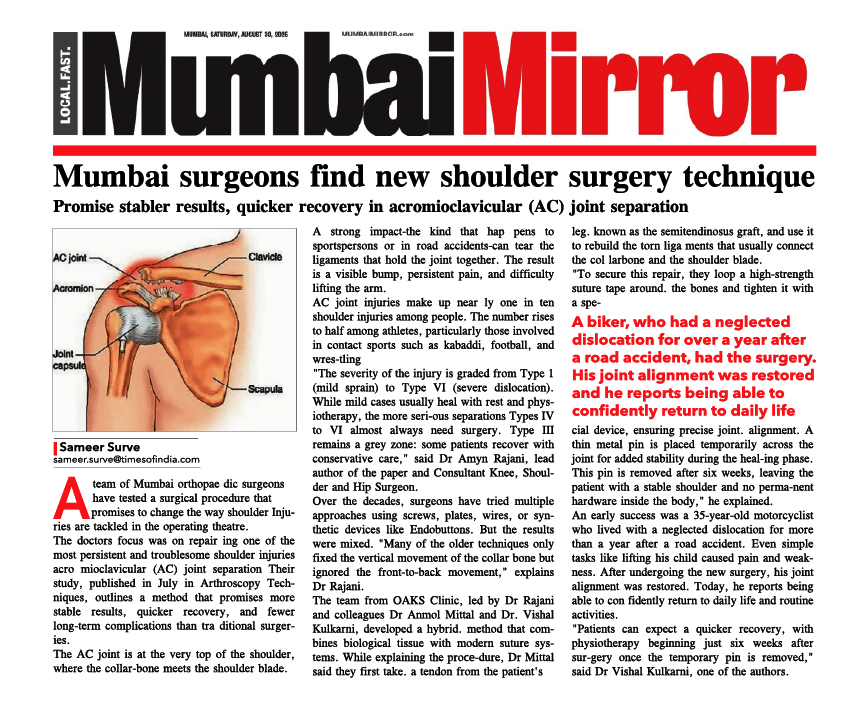

The Clavicle is part of your shoulder and connects your rib cage to your arm.

The Clavicle lies above several important nerves and blood vessels. However, these vital structures are rarely injured when the Clavicle breaks, even though the bone ends can shift when they are fractured.

The clavicle is a long bone and most breaks occur in the middle of it. Occasionally, the bone will break at its ends, where it attaches at the ribcage or Shoulder blade.